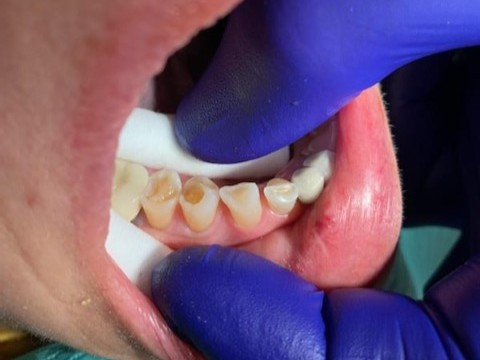

4

Posterior DentXpinTM repair.